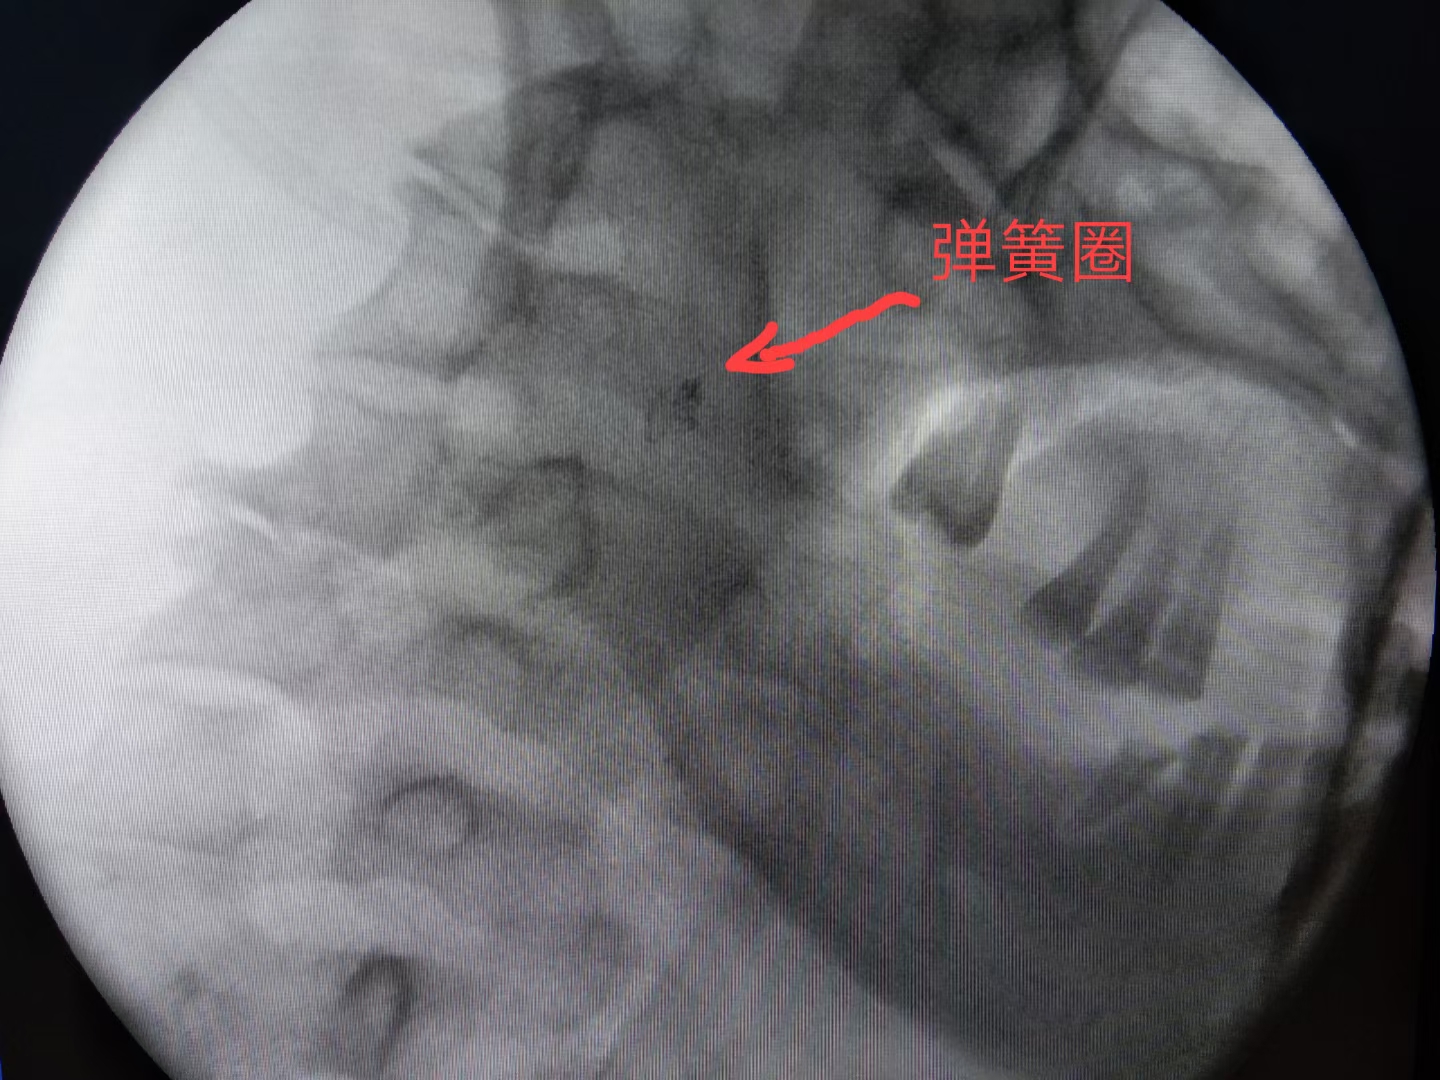

最终,颗粒+弹簧圈完美栓塞。出血停止,患者生命体征平稳。